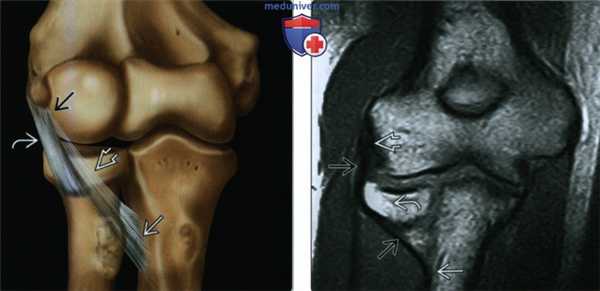

(Слева) На фронтальной МРТ Т2ВИ FS нормального переднего пучка локтевой коллатеральной связки определяется несколько повышенный сигнал в проксимальной части связки около ее прикрепления к плечевой кости, который не следует путать с разрывом.

(Справа) На фронтальной MPT Т2ВИ F5 у бейсбольного питчера определяется внутритканевой разрыв переднего пучка локтевой коллатеральной связки. Вокруг связки и миосухожильной единицы общего сгибателя-пронатора имеется отек. (Слева) На фронтальной МРТ PD ВИ FS у футбольного квотербэка колледжа 20 лет виден отек около проксимальной локтевой коллатеральной связки с разрывом волокон в месте отхождения от плечевой кости.

(Справа) На фронтальной МРТ РDВИ FS у этого же пациента несколько кпереди определяется проксимальный разрыв локтевой коллатеральной связки и субхондральный ушиб головки плечевой кости, указывающий на вдавленное повреждение латерального края локтевого сустава. Такой тип повреждения встречается часто у спортсменов-метателей. (Слева) На фронтальной МРТ PD ВИ FS у этого же пациента кпереди определяется неоднородность дистальных волокон локтевой коллатеральной связки, которая, вероятно, является более хроническим симптомом. Острая травма на фоне хронического повреждения с разрывами локтевой коллатеральной связки является типичной у спортсменов-метателей высокого разряда.